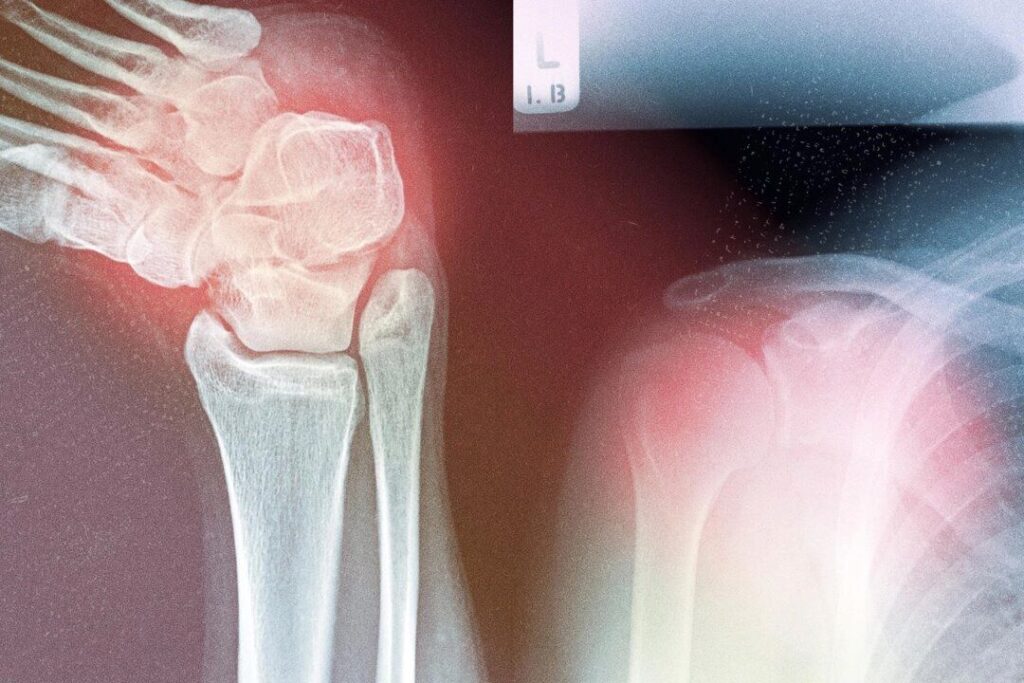

なぜ筋骨格系疾患が増加しているのか — その根本原因と対処法

残念ながら、変形性関節症、骨粗鬆症、痛風、サルコペニア、関節リウマチなど多くの筋骨格系疾患に対して、こうした包括的なアプローチは一般的ではありません。これらの疾患は高齢化とともに急速に増加しており、現在、アメリカでは1億2,100万人以上が影響を受けています。深刻な問題が発生する前に、個別化された全身的なサポートへの移行が必要です。

慢性の筋骨格系疾患は現在、世界的に障害の主要な原因となっています。これらの状態は運動能力を低下させるだけでなく、生活の質を損ない、転倒や骨折、入院のリスクを高めます。

2021年には、約6億700万人が変形性関節症を抱えており、これは1990年と比較して137%の増加です。関節リウマチと痛風も、それぞれ125%、150%増加しています。

これらの疾患にかかるコストは非常に高く、たとえば骨粗鬆症による骨折1回の平均治療費は21,800ドルを超えます。